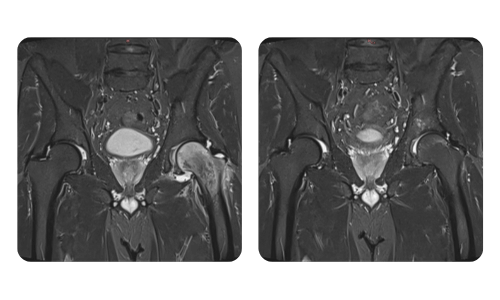

The progress of our patients, measured before and after hyperbaric therapy, reflects the efficiency and positive impact of the treatment. Discover documented results of hyperbaric therapy at Hyperbarium Oradea clinic, based on clinical evaluations and objective data that highlight significant improvements in various conditions.